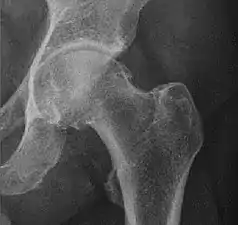

Adults

Landmarks

In the adult hip there are important landmarks to be recognized on plain film radiographs:[3]

- The iliopectineal or iliopubic line is formed by the arcuate line of the ilium and the superior border of the superior pubic ramus up to the pubic symphysis. It conforms to the inner margin of the pelvic ring and it is part of the anterior column of the acetabulum.

- The ilioischial line of Köhler begins at the medial border of the iliac wing and extends along the medial border of the ischium to end at the ischial tuberosity. It is part of the posterior column of the acetabulum.

- The acetabular floor.

- The teardrop represents a summation of shadows. Its medial aspect corresponds to the inner cortex of the pelvis and the lateral edge with the acetabular notch and the anteroinferior portion of the quadrilateral plate. It is not present at birth but gradually develops due to pressure of the femoral head.